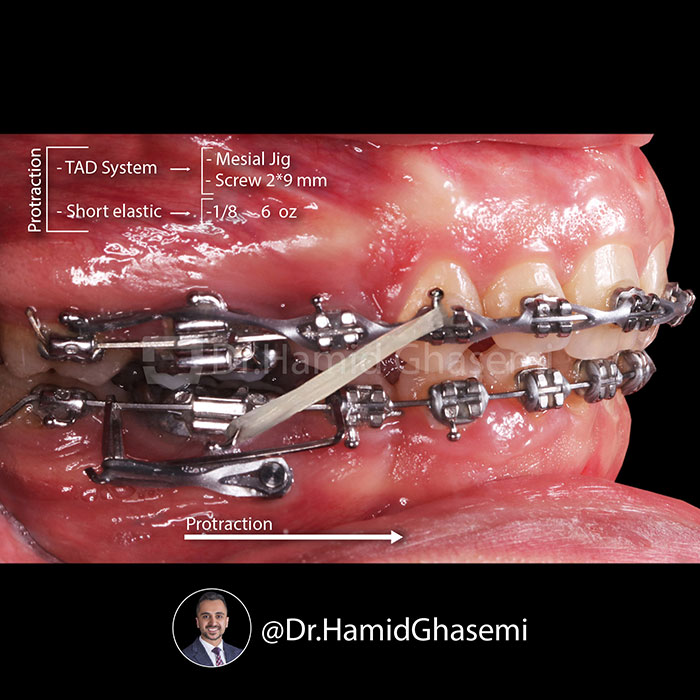

ارتودنسی دندان نهفته؛ راهحلی برای درمان مشکلات پنهان دندانها10 آذر 1403 - 6:20 ب.ظ